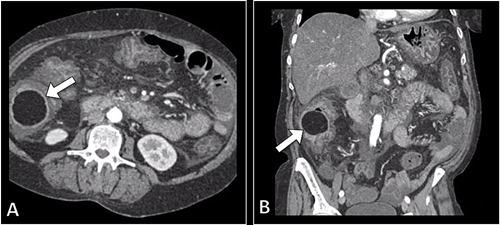

基于上述表现和检查结果,初步诊断为急性阑尾炎。行腹部CT扫描和造影以确认诊断,结果显示结肠壁增厚并伴有皱襞水肿,提示伪膜性结肠炎。此外,在盲肠中发现大小为6cm的腔内病变,病变边界清晰,为均匀脂肪密度无固体成分。该病变肿块造成部分结肠梗阻,提示为盲肠脂肪瘤(图1)。

(图1 CT检查)

患者随后接受腹腔镜探查,行盲肠局限性阶段性切除伴阑尾切除术。切除组织病理学检查结果显示为盲肠脂肪瘤伴急性阑尾炎。患者术后恢复良好,随访无症状。